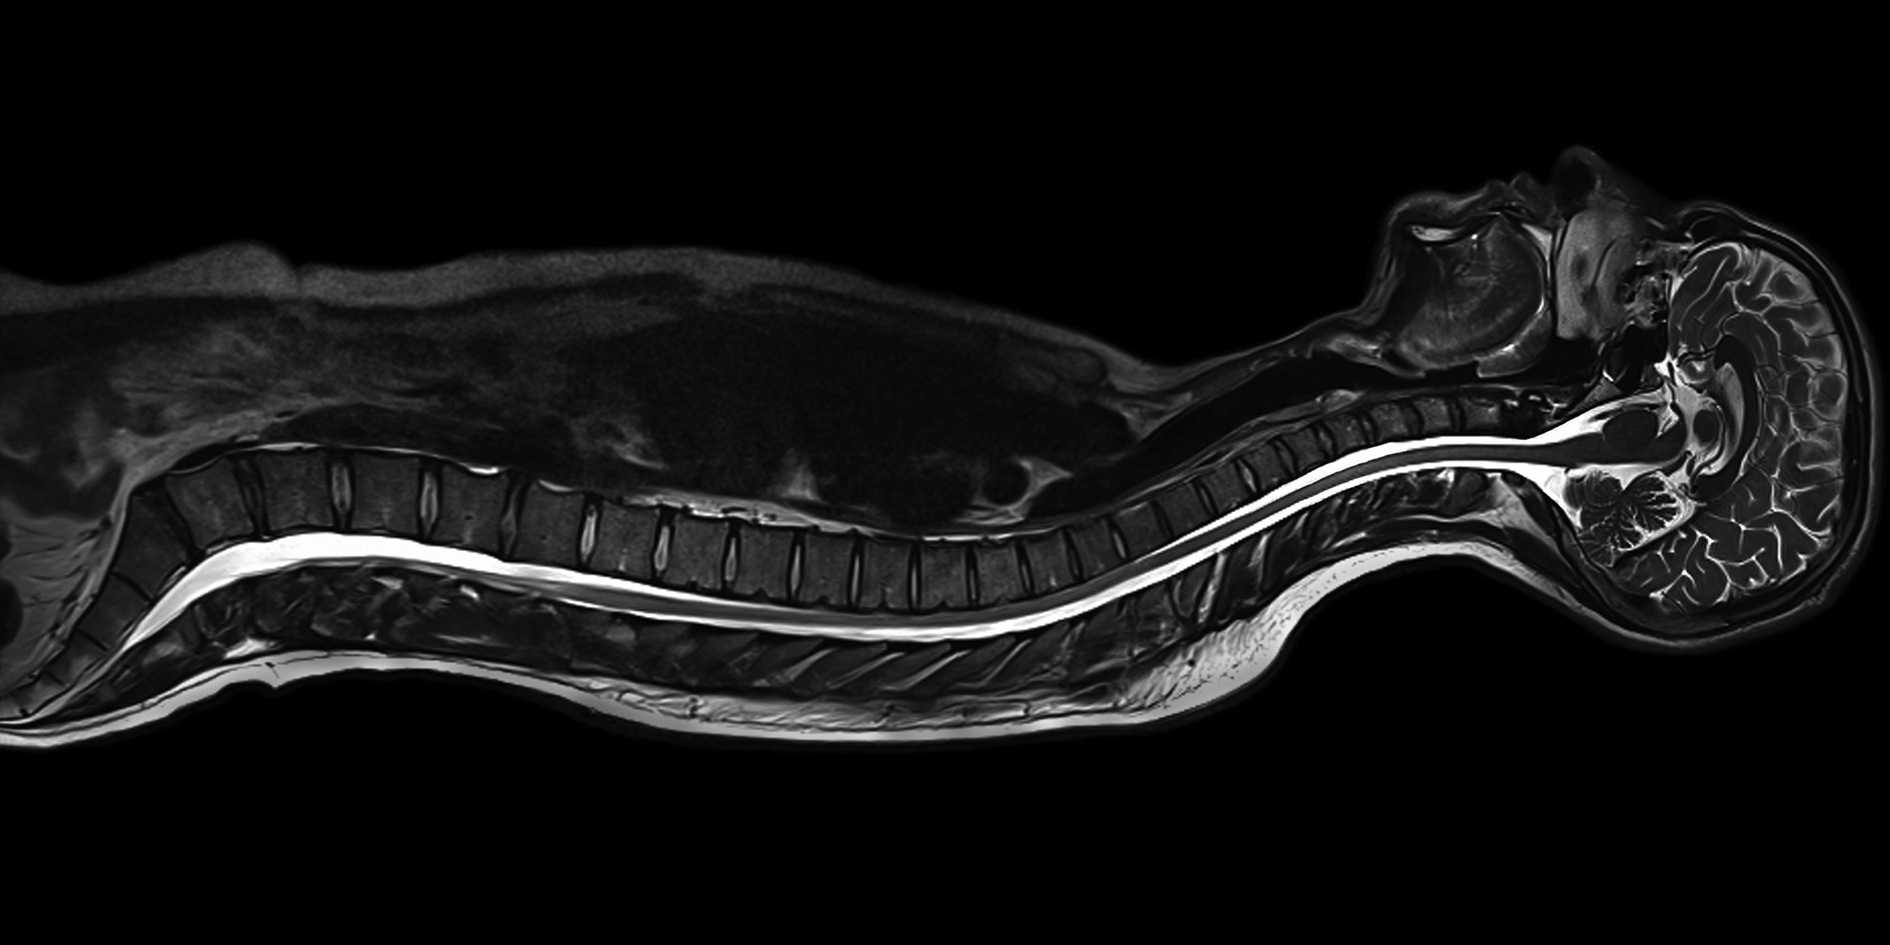

Top Speed was presented a challenge by a local Radiology Group to manufacture a computer that would improve their imaging services and complement the new high definitions monitors they were acquiring. Additionally fully utilizing and improving the functionality of the new PACS CareStream software was also a goal./p>

This particular Radiology Group provides numerous diagnostic services to the Northern Nevada area; MRI, PET/CT, Digital Mammography and Women's Services, Computed Tomography, Ultrasound, Nuclear Medicine, X-Ray & Digital Flouo, Dexa: Osteo Bone Density Testing and Body Fat Analysis / Health Check. They've taken great care in being the frist to bring new imaging technologies to the region.

Rather than trying to reinvent the wheel Top Speed first performed detailed research into the current technology being imployed by radiology departments, both in private practice and in hospital settings. Our main concern was locating where improvements could be made to lessen the amount of time taken, and thereby wasted, as radiologsts waiting for images to render and be viewable and therefore ready for diagnosis by the radiologist. Once we had a good feel for the existing technologies our engineers tackeled the issue of making sure the hardware was up to handling the advancements int he PACS software system that was to be installed. A frequent issue noted was that no exisiting systems seemed to be able to use the PACS system to it's full capacity.

The RadDx computer system build took into account the need for accelerated performance when needed and the need to be efficient at all other times. High speed server grade memory was used for reliability, no hospital or Radiology Group has time for anything less. Absolutely no spinning hard drives to avoid the risk of mechanical failure on a critical piece of hardware; instead we used Maximum IOPs SSD drives for both speed and efficiency when rendering images. Once our basic configuration was set, we added all the specific requirements needed by our local Radiology Group. Details on the basic RadDx computer configuration are available below.

The final step was implementing the RadDx computer in the Radiology Group's new configuration, upgraded monitor viewing for optimal diagnosis from the Radiologists and assisting with any hardware issues during the implementation of the new CareStream PACS system. Initial hardware installation went without issue; the setup being used within this group had changed the standard monitor viewing to a new view far more friendly to the eyes of the diagnostic Radiologists. The CareStream PACS system implentation ran into a challenge when the software load balancer did not do what was necessary. As a result Top Speed recommended going with a Kemp hardware Load Balancer. This was an option not fully tested with CareStream, but at the insistance of the Radiology Group based on our recommendation this solution was tried with excellent results.

Prior to leaving one of the CareStream implementation engineers informed us that "We've never seen our software run so fast." Our RadDx Workstation could hardly have received a better complement or higher praise that our research and hardware configuration had come together so successfully.